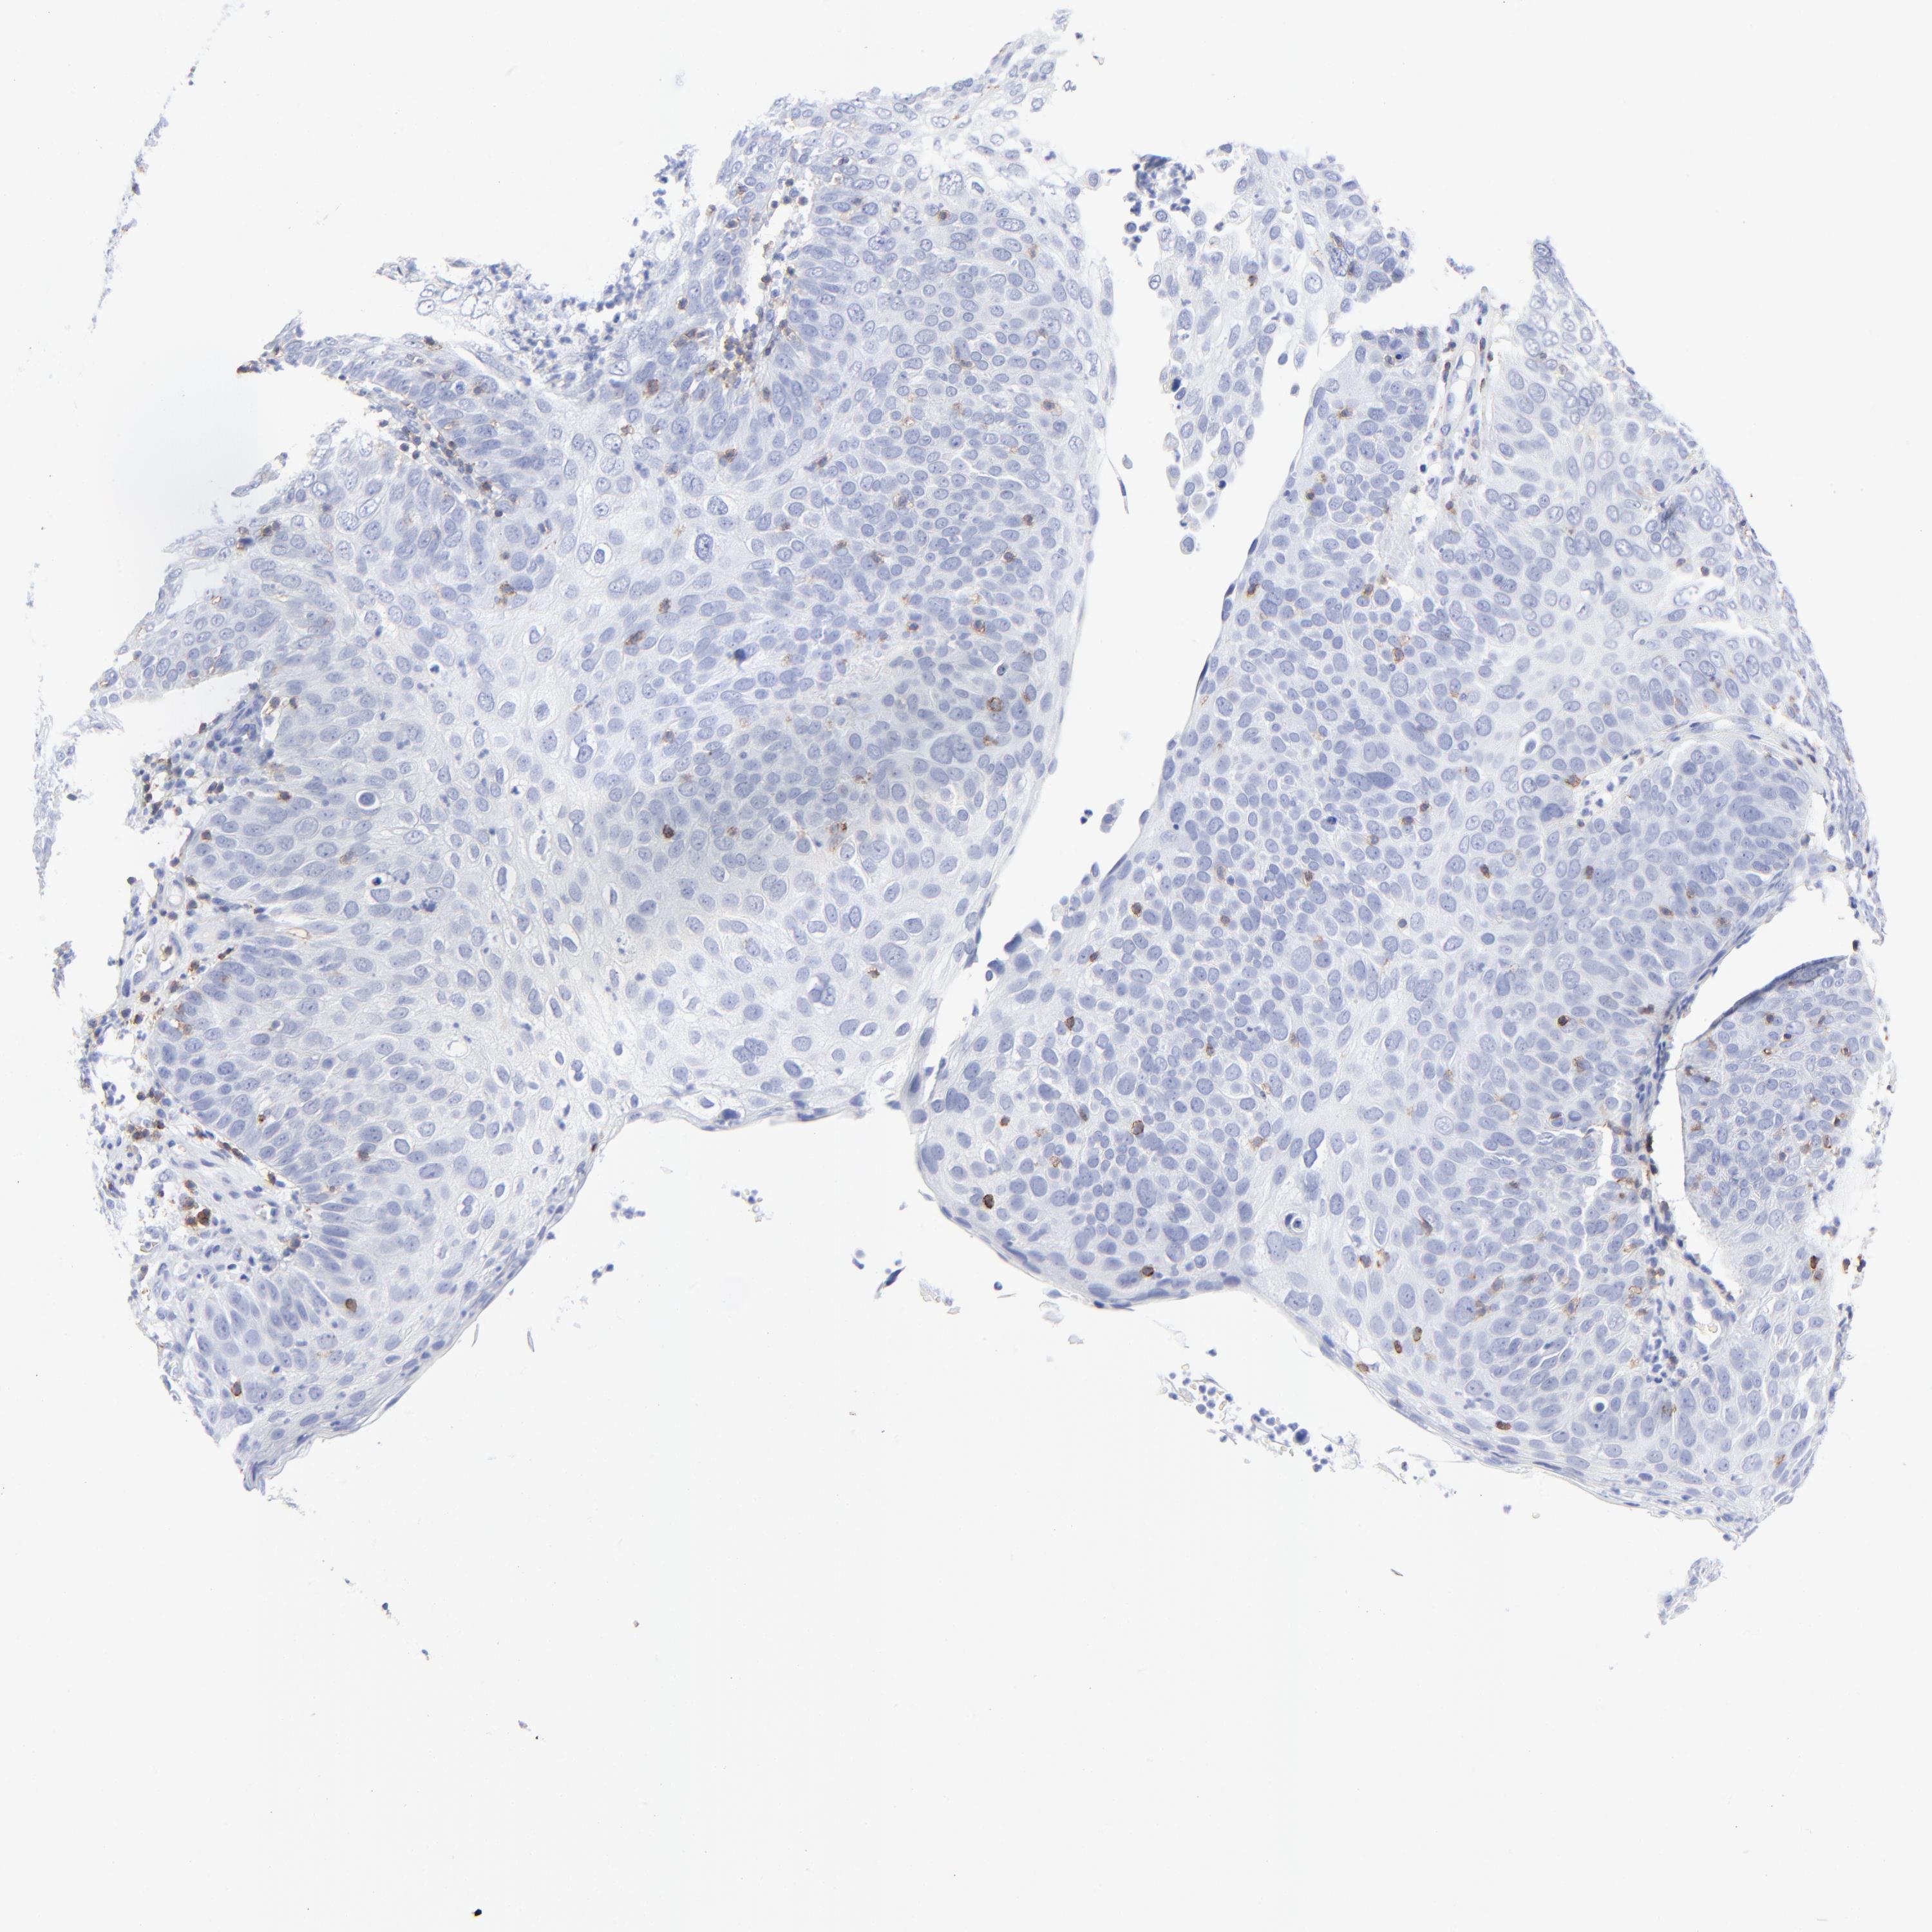

SKIN CANCER - Protein expressioni

A mouse-over function shows sample information and annotation data. Click on an image to view it in a full screen mode. Samples can be filtered based on level of antibody staining by selecting one or several of the following categories: high, medium, low and not detected. The assay and annotation is described here.

Antibody stainingi

Antibody staining in the annotated cell types in the current human tissue is reported as not detected, low, medium, or high, based on conventional immunohistochemistry profiling in selected tissues. This score is based on the combination of the staining intensity and fraction of stained cells.

Each image is clickable and will lead to virtual microscopy that enables deeper exploration of all samples and also displays staining intensity scores, fraction scores and subcellular localization as well as patient and tissue information for each sample.

Antibody HPA003494

Antibody CAB003816

Squamous cell carcinoma, NOS

Basal cell carcinoma